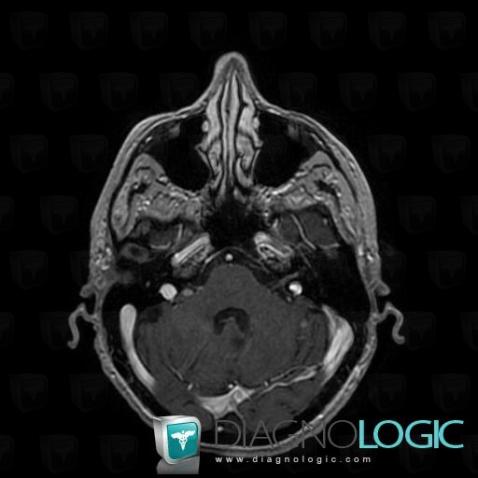

Les images ci-dessous illustrent ce dossier pour les diagnostics Carcinose méningée, Méningite carcinomateuse, pour les modalités (IRM)

Voici les informations spécifiques à l'image clé ci dessus:

- Diagnostic Méningite carcinomateuse, Localisation(s) Espaces peri cérébraux infratentoriels, comportant les gammes Anomalie des citernes de la base